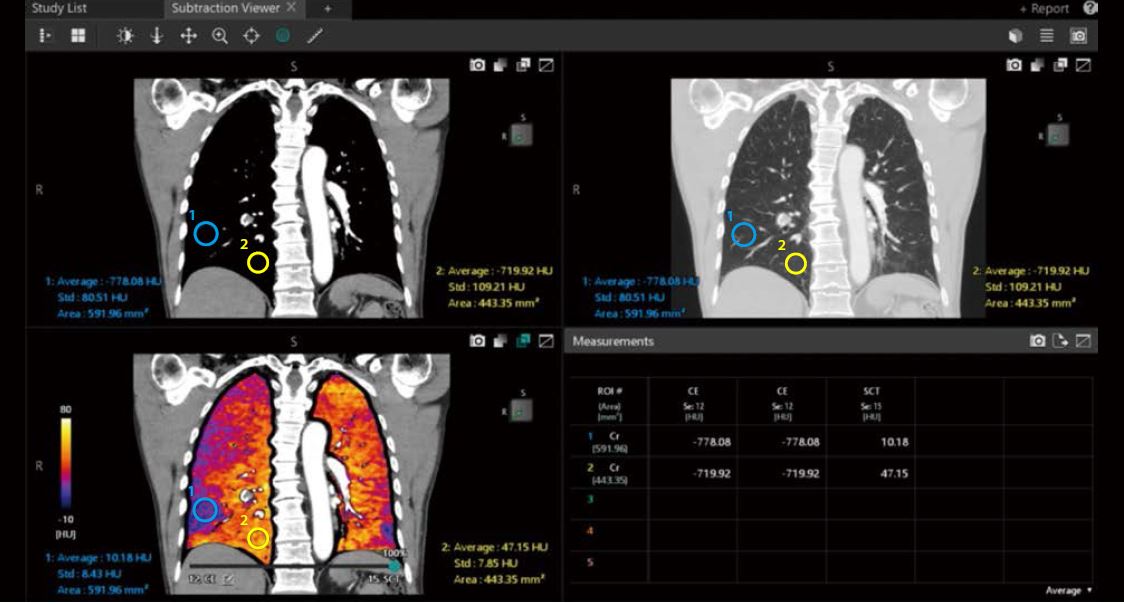

Subtraction Viewer (Програмне забезпечення для перегляду йодних карт)

При використанні Subtraction Viewer* також можна інтерактивно прокручувати кольорові карти йоду, синхронізовані із зображеннями у градаціях сірого, для швидкої візуалізації та виявлення ділянок із гіпоперфузією.

• Автоматичні навісні макети

• Синхронізований перегляд усіх показаних зображень

• Геометричні вимірювання та вимірювання щільності по шкалі Хаунсфілда